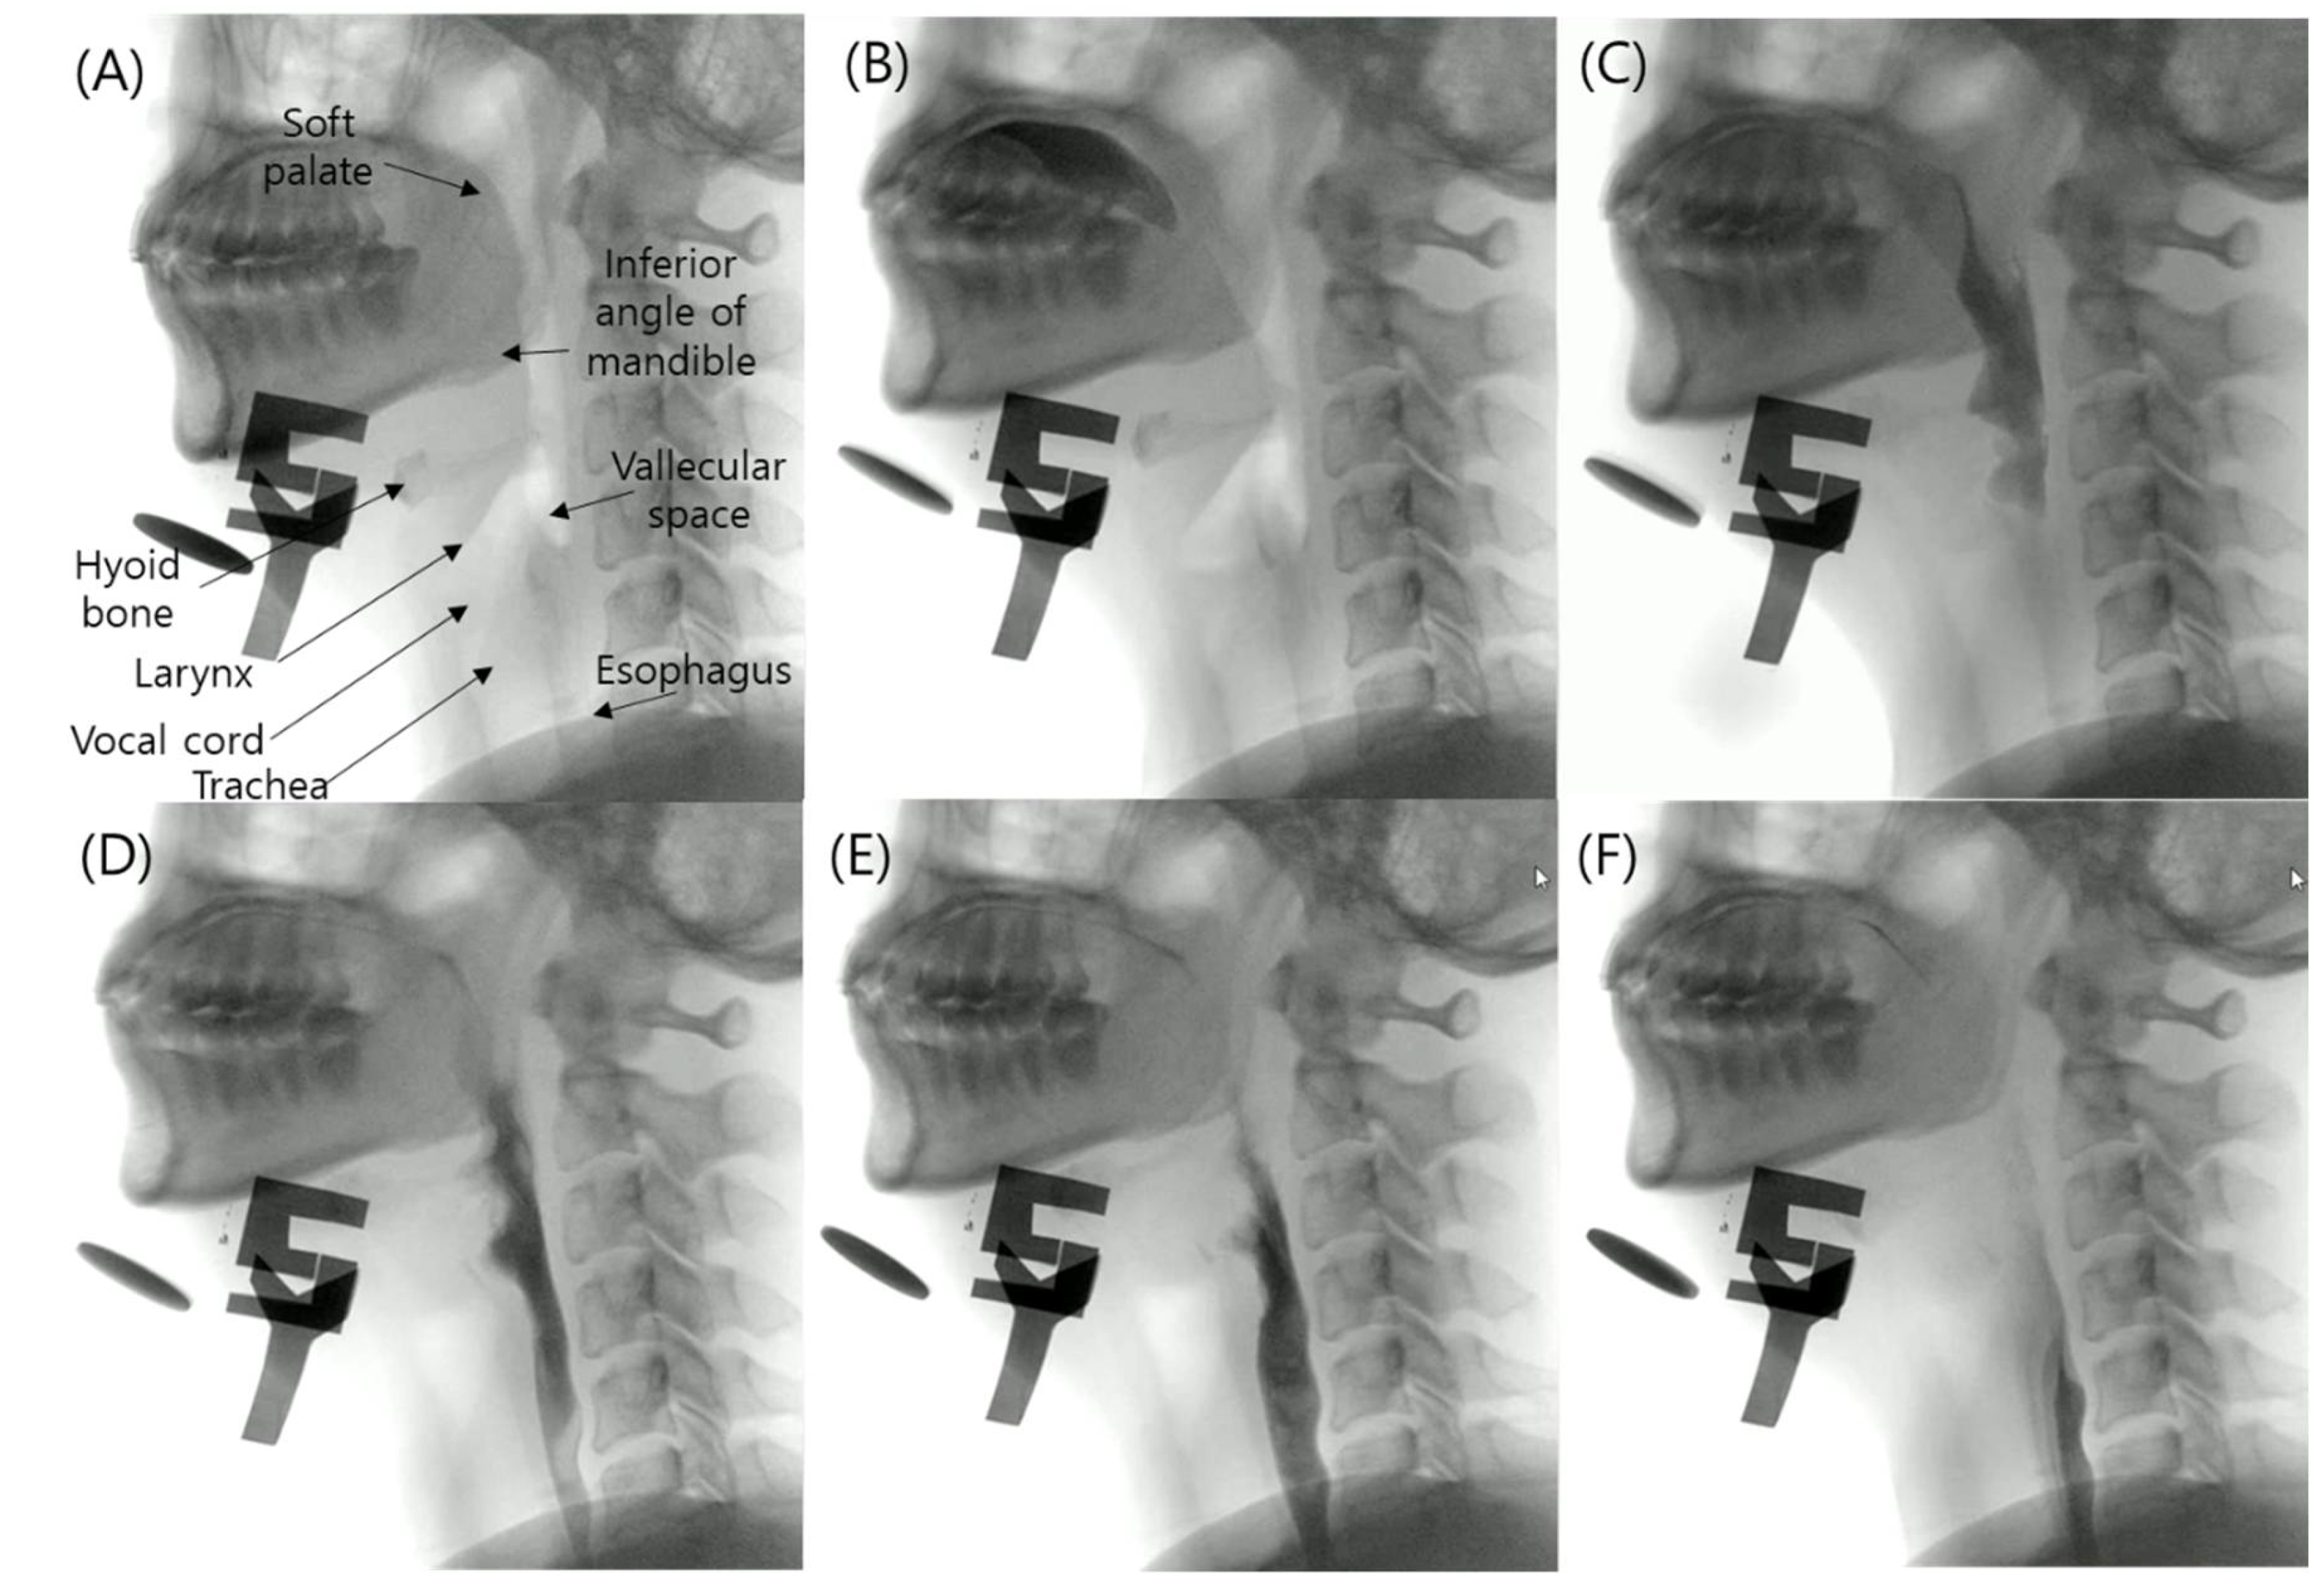

2.2. Datasets